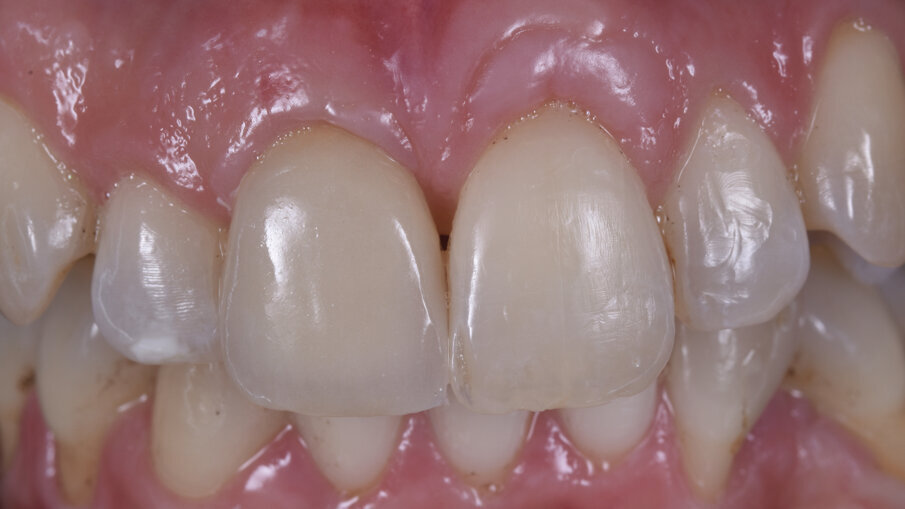

A distanza di 4 mesi dalla chirurgia implantare abbiamo ottenuto sul piano frontale un ottimo livellamento delle parabole gengivali con il ripristino di un’anatomia corretta e ideale sia dei margini gengivali di 1.1 e 2.1 sia delle papille interdentali mesiali e distali alla corona sull’impianto dell’1.1 (Fig. 15), mentre la rimozione del provvisorio avvitato ha permesso di evidenziare sul piano trasversale il condizionamento dei tessuti molli, la perfetta integrazione della matrice Fibro-Gide (Geistlich Pharma AG, Wolhusen, Switzerland) e la vascolarizzazione del sito con fibre circonferenziali ripristinando la corretta ideale anatomia attorno a un corona su impianto dal centro verso la periferia con epitelio connettivale, epitelio giunzione e epitelio sulculare (Figg. 16, 17); il nuovo livello di frequenza di risonanza è salito fino a 81 ISQ.

Dopo una prova estetica del colore e della tessitura superficiale, e un controllo radiografico bidimensionale, il caso è stato finalizzato posizionando il restauro in ceramica avvitato che è stato serrato con torque di 25 N /cm (Fig. 19). Si è ottenuto un mimetismo ideale e completamente naturale sia per quanto riguarda la componente bianca del restauro (ceramica) sia per la componente rosa (profilo, spessore e anatomia dei tessuti molli) risultando in un’estetica eccellente (Figg. 20-24).